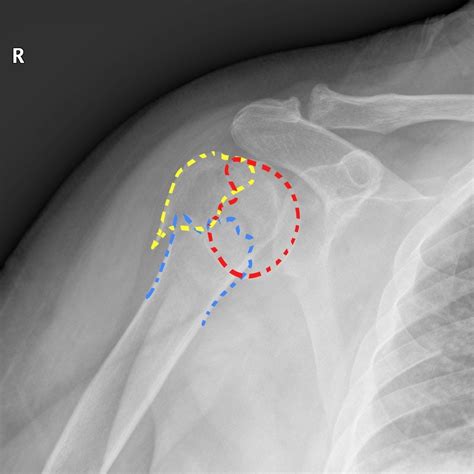

• Imaging Tests: X-rays are the primary imaging tool used to diagnose proximal humerus fractures. In some cases, additional tests such as CT scans or MRIs may be ordered to provide more detailed images.

Classification of Proximal Humerus Fractures

Proximal humerus fractures are classified based on the location and pattern of the fracture. The most common classification systems include:

• Neer Classification: This system categorizes fractures based on the number of parts involved (one, two, three, or four parts).

• AO/OTA Classification: This system uses a more detailed coding system to describe the fracture pattern and severity.